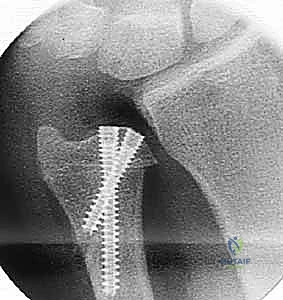

الخطوة 3: التخطيط الهندسي والقطع العظمي (Osteotomy)

باستخدام أدوات جراحية متقدمة وقوالب قطع مخصصة، يقوم الدكتور هطيف بإزالة شريحة دقيقة جداً من عظم الزند (يتراوح سمكها عادة بين 2 إلى 5 مليمترات، بناءً على القياسات المأخوذة من الأشعة السينية مسبقاً). يتم القطع عادة بشكل مائل (Oblique) لزيادة مساحة السطح العظمي وضمان التئام أسرع وأقوى.

الخطوة 4: التثبيت الديناميكي (Dynamic Compression)

بعد إزالة الجزء الزائد، يتم تقريب طرفي العظم المقطوعين معاً. هنا تبرز مهارة الجراح؛ حيث يستخدم الدكتور هطيف شريحة معدنية متخصصة (Dynamic Compression Plate) ومسامير من التيتانيوم لتثبيت العظم بقوة. هذه الشريحة مصممة لضغط نهايات العظم معاً، مما يحفز الخلايا العظمية على الالتئام السريع.